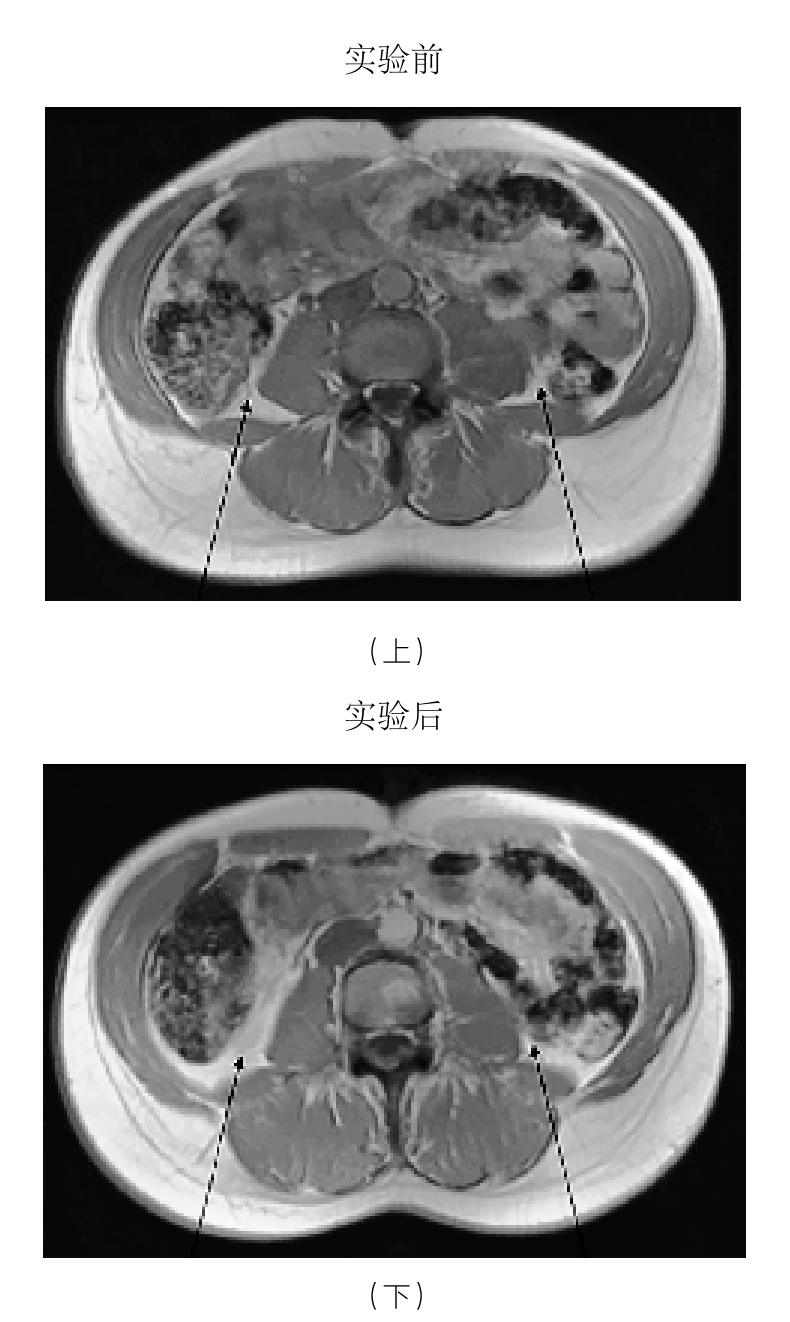

过多的脂肪,尤其是内脏内部和周围的脂肪会引发慢性轻度炎症。这是久坐引发慢性轻度炎症的第一种方式,这一过程的机理提醒我们,久坐会带来危险,而原因很可能仅仅就是这一行为造成了体重的增加。有一个事实值得反复强调,那就是坐在舒适的椅子上时,肌肉几乎不承受任何压力。而即使是蹲着或者跪着也需要肌肉参与,哪怕只是站着,每小时都会多消耗8大卡能量,像把洗好的衣物叠起来这种轻量活动每小时要比坐着多消耗100大卡能量。 36 这些能量累积起来的效应不可低估。对于我而言,每天花5小时仅仅从事一些哪怕是非锻炼类的低强度身体活动,所消耗的能量就相当于跑步一小时。所以,如果我坐着而没有活动,那么我午饭摄入的热量就很有可能转化成了脂肪,而不是被燃烧掉。丹麦的研究人员付费招募了一组健康的年轻人,让他们像名副其实的“沙发土豆”那样,每天走动不超过1 500步(约1.6千米),持续时间为两周。这项实验的结果或许有一些警示作用。研究人员对实验前后被试的腹部进行了扫描,对比结果显示,这些男性被试的内脏脂肪在两周内增加了7%(见图3-2下图)。 37 更加令人不安的是,这些被试在脂肪增加的同时,还开始表现出慢性轻度炎症的典型症状,其中包括分解餐后血糖的能力降低。需要说明的是,这个实验只是对久坐的间接后果进行研究。当然,这并不是说久坐是造成这些丹麦年轻人变胖的唯一原因。身体长时间不活动外加热量摄入过多,共同造成了过多内脏脂肪的堆积,继而点燃了慢性轻度炎症的“星星之火”。还有一个现象,那就是这些志愿者增加的脂肪大部分是内脏脂肪,这说明他们一直处于压力之下。我们还知道有很多缺乏活动的人其实体重并没有超重,却饱受慢性轻度炎症的困扰。那么,久坐还会通过哪些方式诱发慢性轻度炎症呢?

图3-2 男性被试实验前后的腹部磁共振成像扫描对比图

注:实验前(上图)和经过两周久坐或进行极轻量活动后(下图)。被试的内脏脂肪(箭头所示)在两周内增加了7%。

资料来源:Olsen, R. H.,et al.(2000),Metabolic responses to reduced daily steps in healthy nonexercising men, Journal of the American Medical Association 299: 1261-63. Bente Klarlund Pedersen提供。